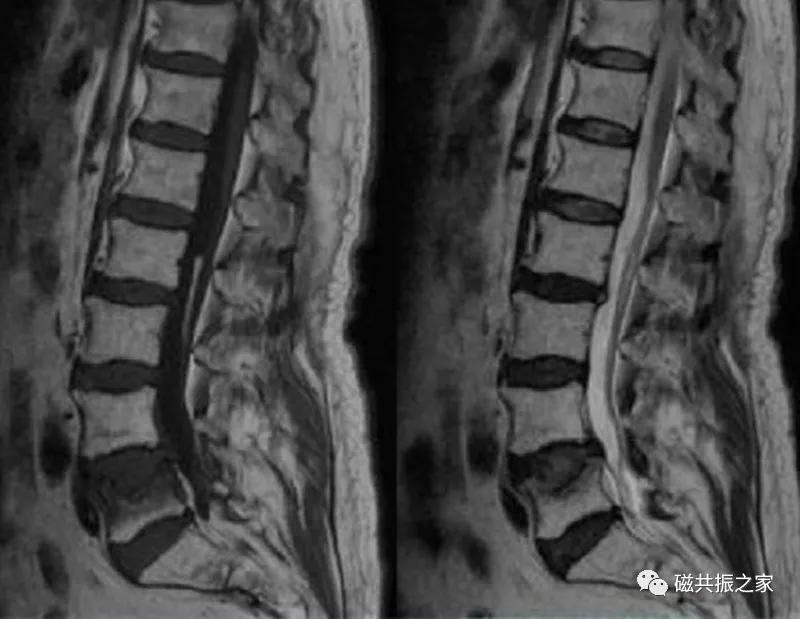

椎体压缩性骨折常成前窄后宽的楔形改变,新鲜骨折(红箭头)常在T1WI呈低信号(出血时可呈高信号),T2WI呈低、中信号,在脂肪抑制的T2WI上呈高信号。椎体陈旧性骨折(白箭头)信号类似于正常椎体信号。如需了解脊柱骨折分型请查阅脊柱骨折的分型。